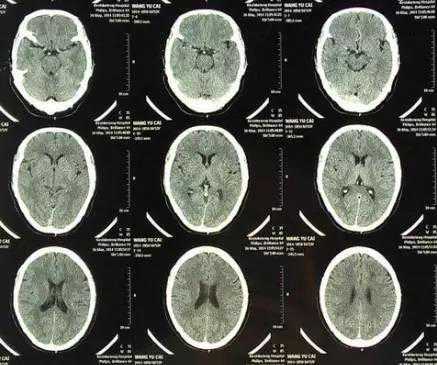

CT像把面包切片看

CT意为X线计算机断层摄影,是用X线束对人体某部进行断层扫描,获得人体被检部的断面或立体图像。CT可以提供人体被检查部位的完整三维信息,可使器官和结构清楚显影,清楚地显示病变。就像把一片面包切成片来看。优点是可以分层看,经计算后可以显示出更多的组织信息。